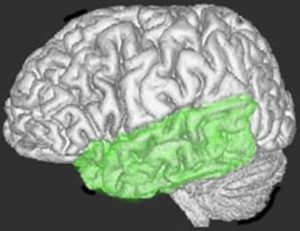

言語野・ウェルニッケ領域

左側頭葉の言語中枢(ウェルニッケ領域)です。上側頭回の後ろの方にあります。ここが侵されると,言葉を聞いても理解できないという感覚失語という症状が出ます。左側頭葉の底面には字を読む能力もあります。